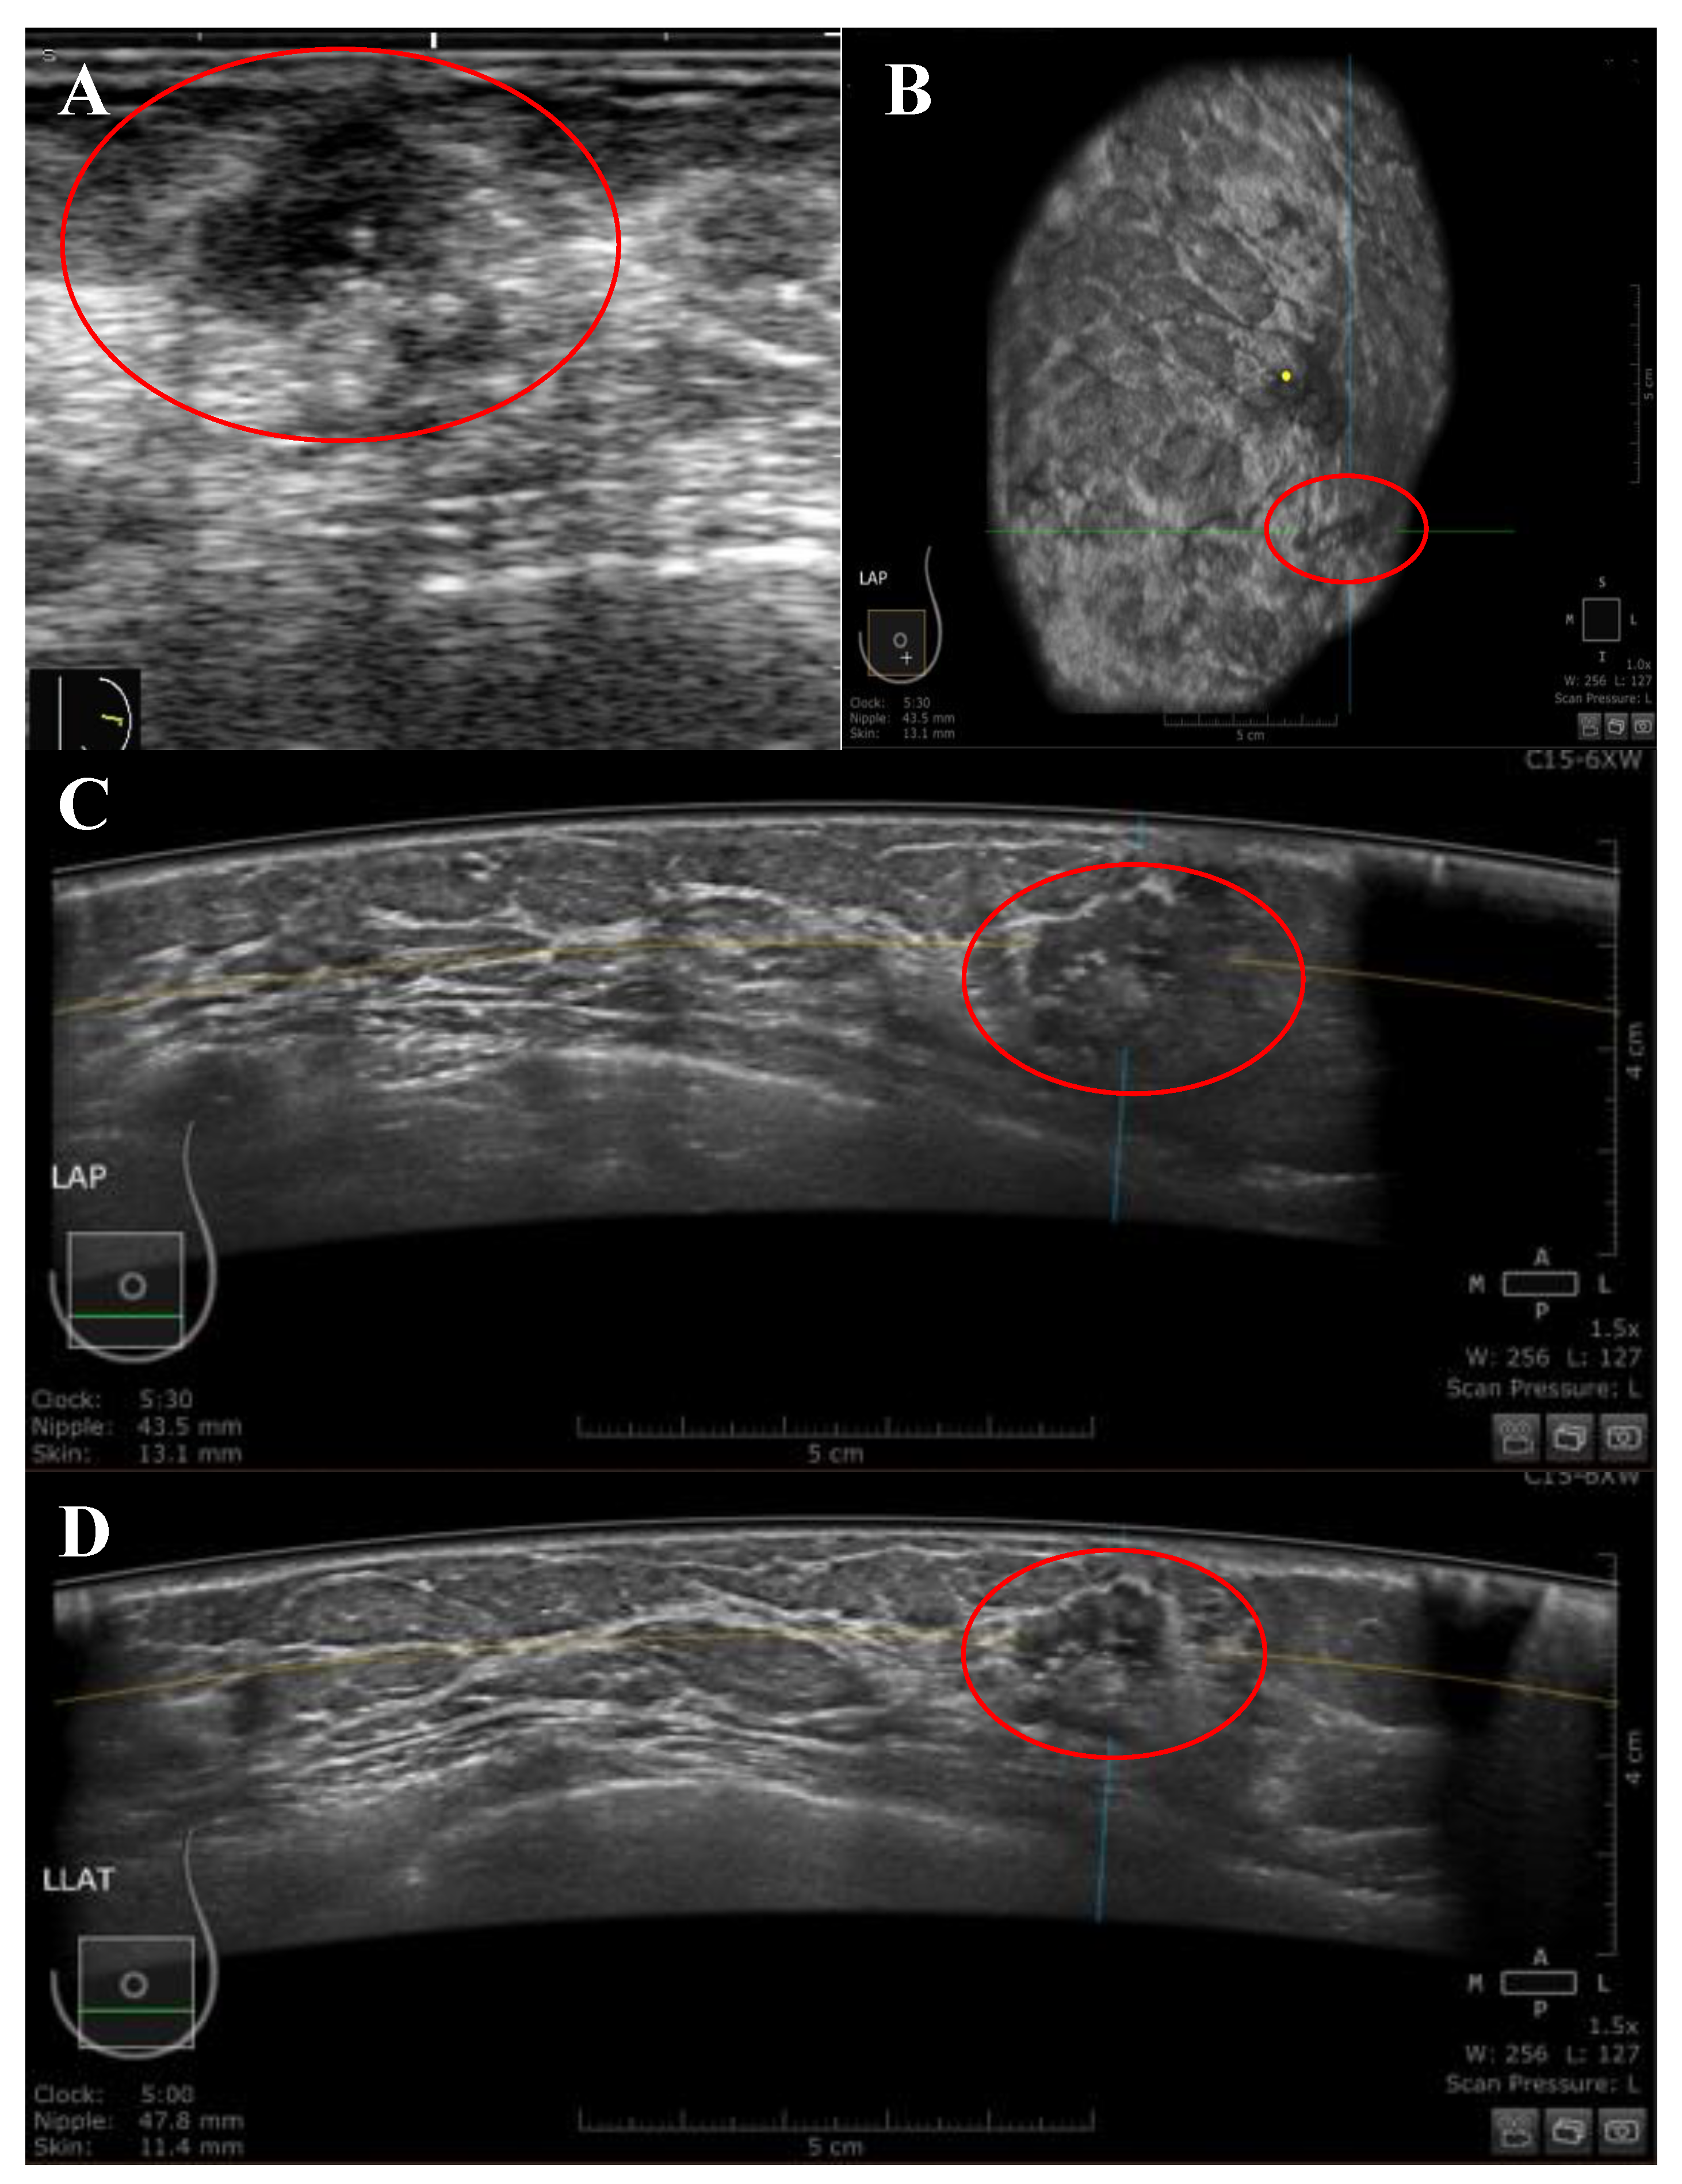

2.2. HHUS

2.3. ABUS